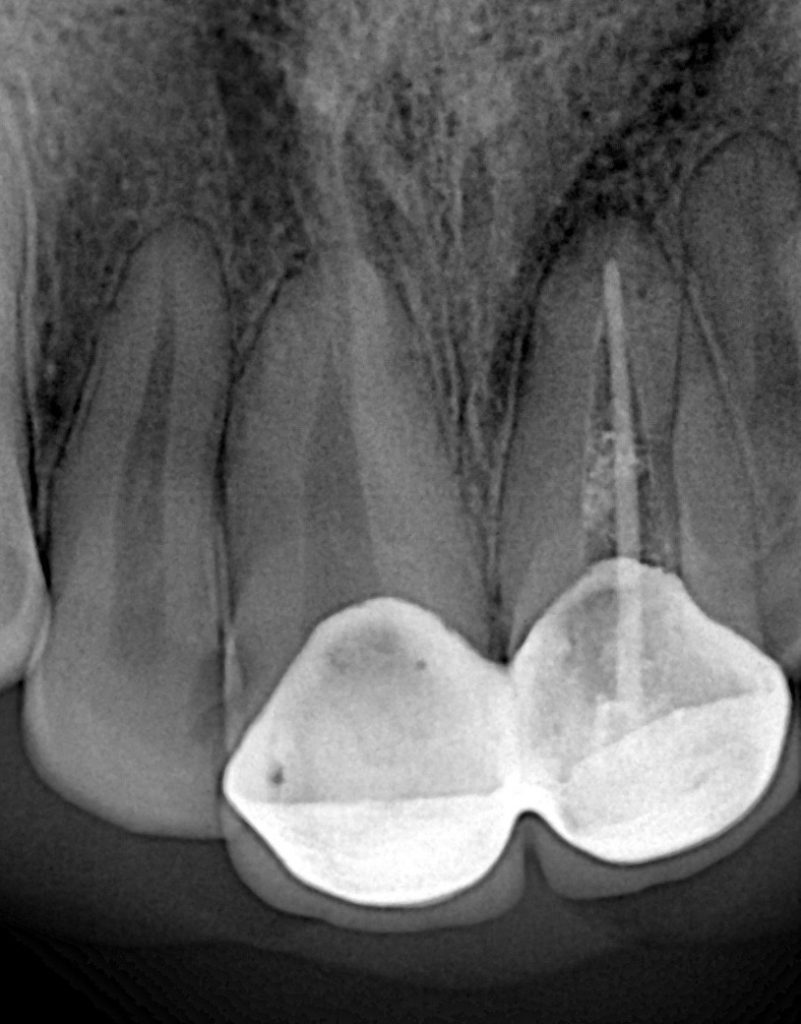

Working length was confirmed using an apex locator and verified radiographically (Fig 8).

After thorough drying, obturation was carried out via the warm vertical compaction technique with gutta-percha and bioceramic sealer (Fig 9-10).